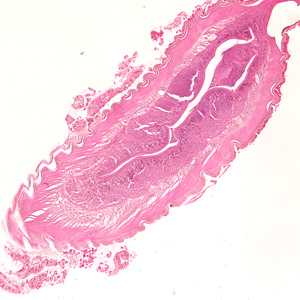

March - 2008 - Case #224

A 47-year-old male with travel history to the Galapagos Islands, Ecuador and Colombia presented to his health care provider with follicular conjunctivitis. A worm-like object measuring approximately 3.0 mm was removed from his eye and sent to a pathology laboratory for analysis.